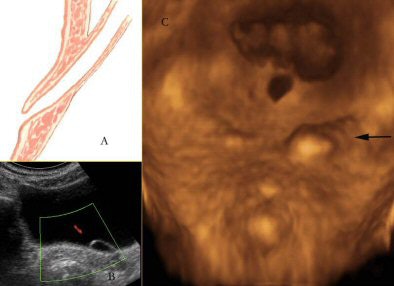

In the urinary bladder, the presence of urine creates a physiological acoustic window to render the urinary bladder wall and the trigone. This helps create virtual cystoscopic views, also known as sonocystoscopic views, of the urinary bladder lumen.

![]() |

| Three-dimensional rendering of the trigone of the urinary bladder. An anatomical illustration (A) of the intramural course of the terminal ureter gets dilated in some cases to form an ureterocele as seen on 2D scan (B). Three-dimensional rendering (C) shows a sonocystoscopic image of the same (arrow), bringing out the elevated left ureteral ridge secondary to the ureterocele in a lucid manner. |